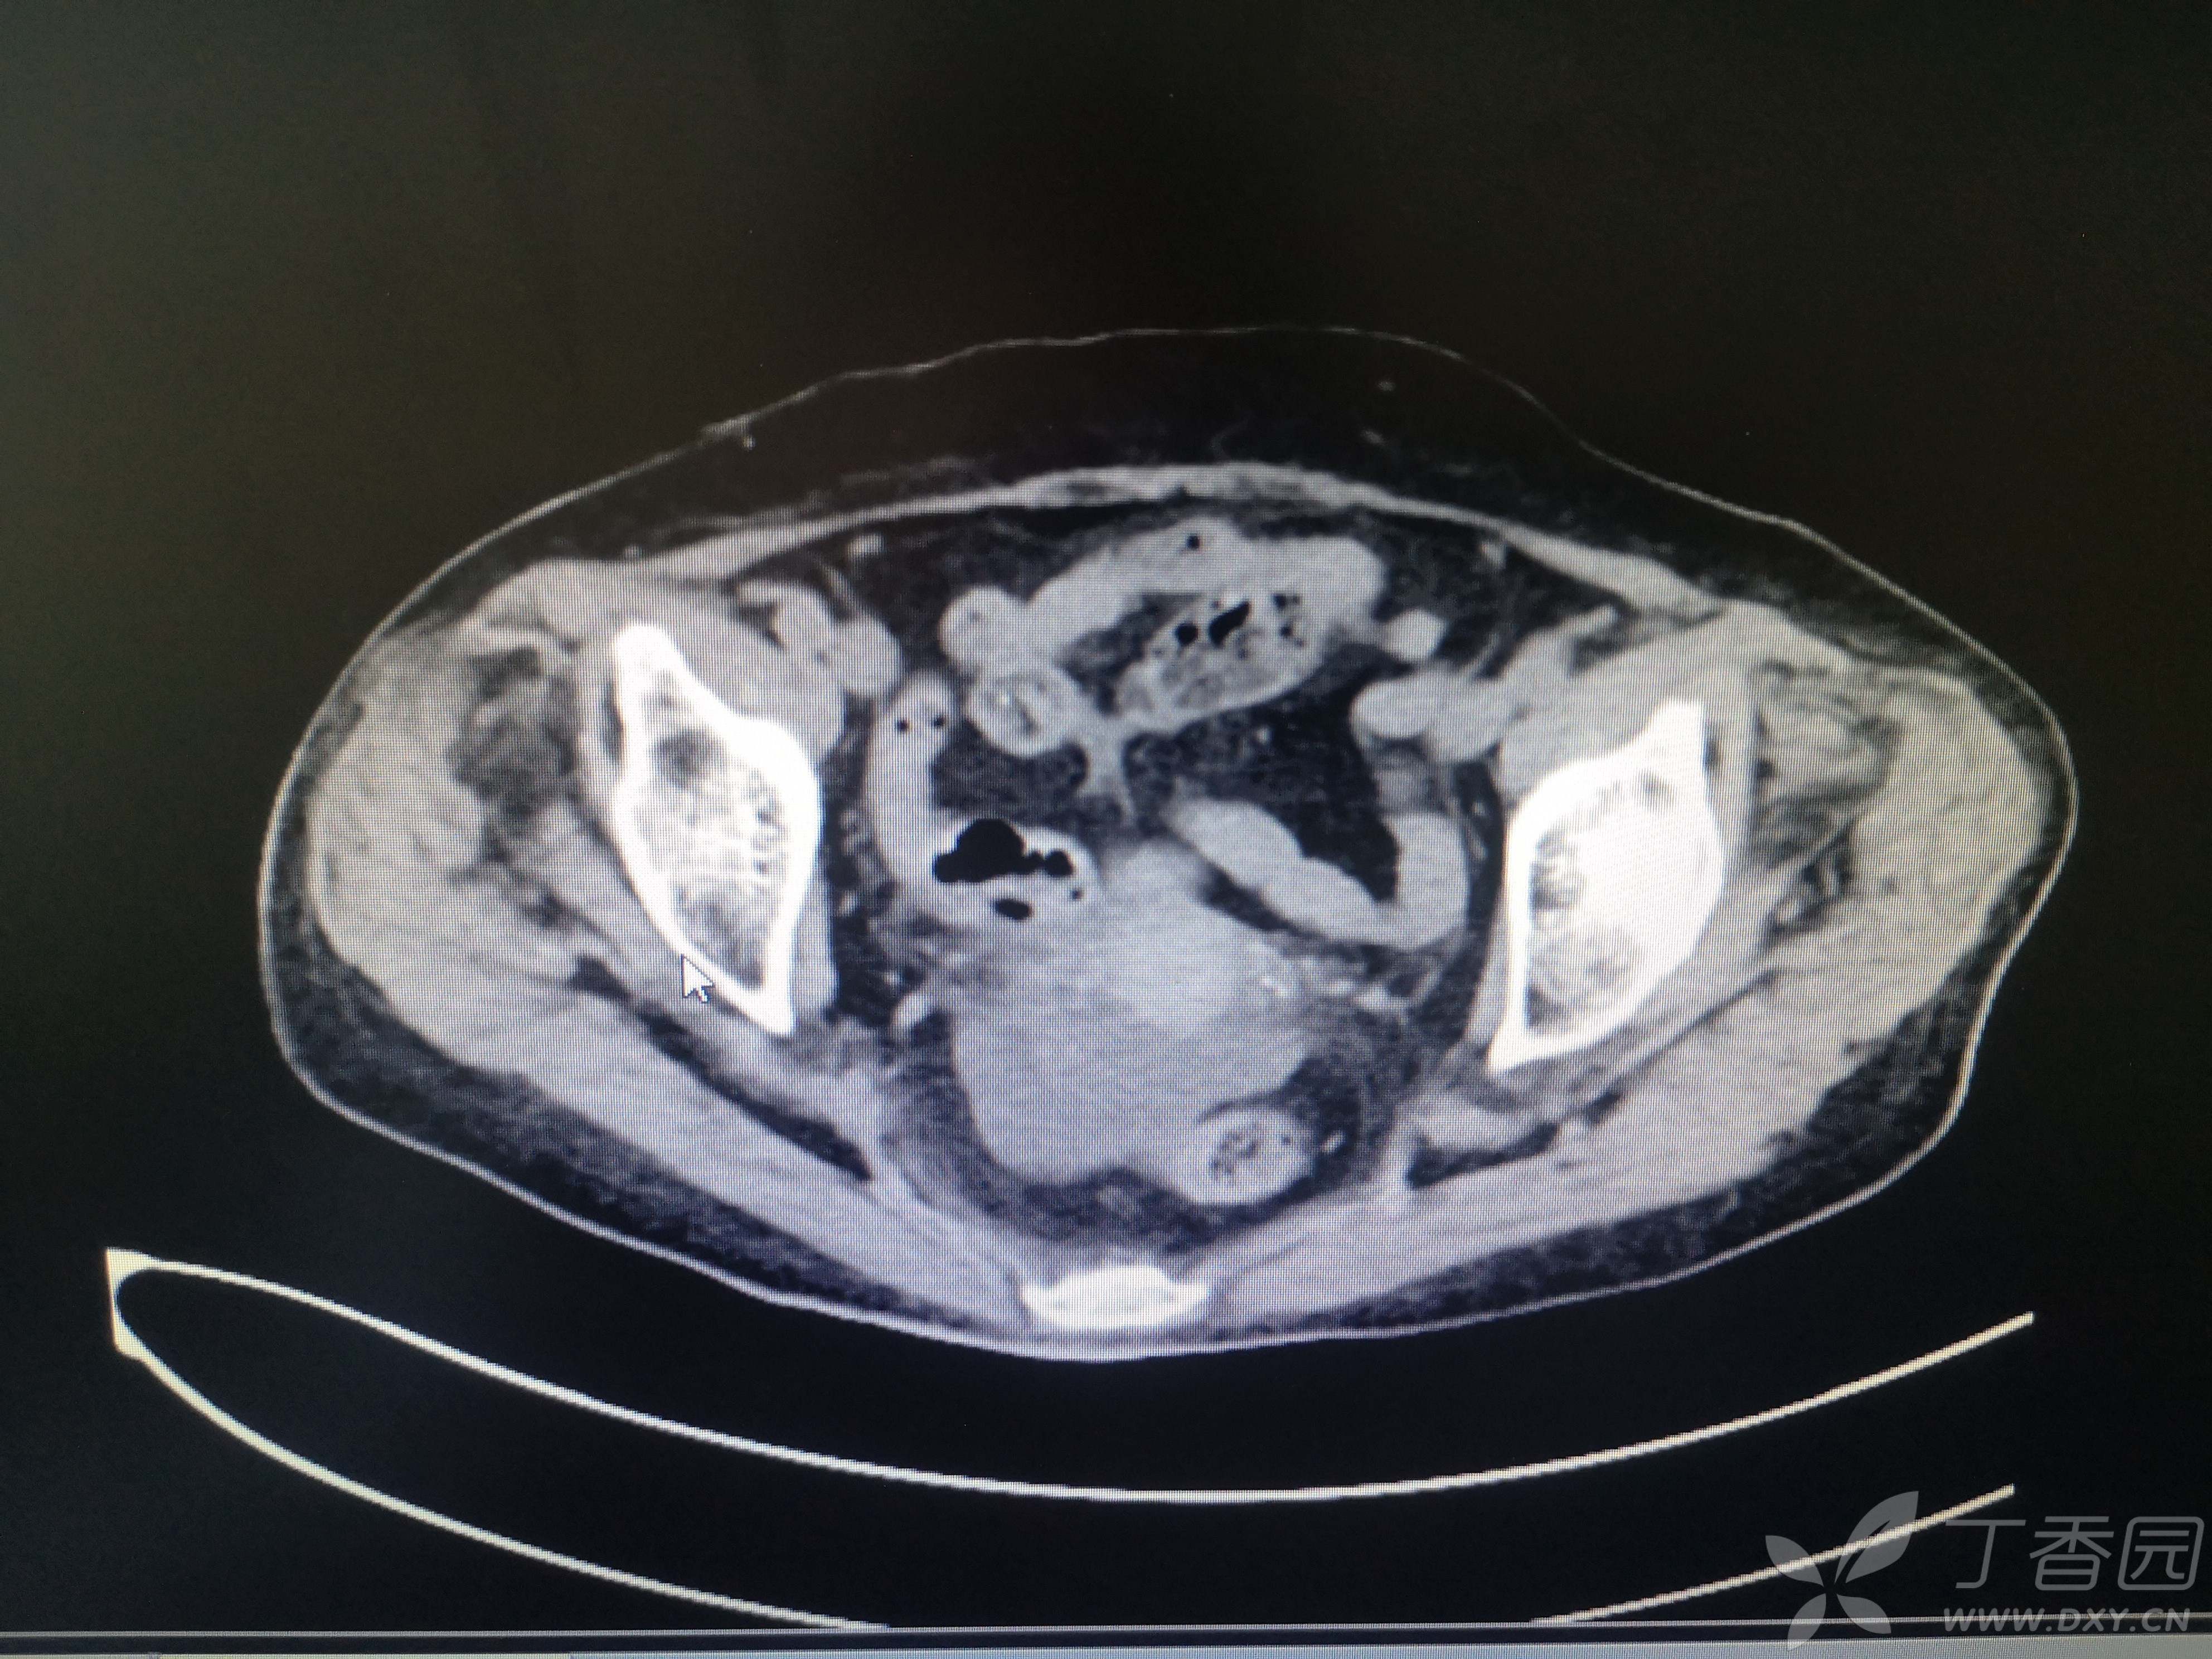

11小时前无明显诱因出现右腹部疼痛,伴恶心、呕吐,呕吐物清稀黏液,急至我院就诊,患者在家属搀扶下步入急诊室,神志清,言语费力,呼吸浅快,口唇、手足皮肤青紫,心电图示快速房颤,血压低至68/48mmHg,脉氧测不出,动脉血气分析PH 7.1,PCO2 13.6mmHg,PO2 135mmHg,Lac15.1mmol/L,HCO3 4.1mmol/L,K 6.11mmol/L。CT、血常规、血凝、生化等结果见图 。

患者CT图像如下

完善CT检查以后收入重症医学科治疗。

入院诊断1.感染性休克2.多器官功能衰竭(急性肝功能不全 急性肾功能不全 心功能不全 凝血功能障碍)3.急性胆囊炎4.电解质代谢紊乱5.代谢性酸中毒6.肺部感染7.心房颤动8.多发性肾囊肿9.冠心病10.盆腔积液。